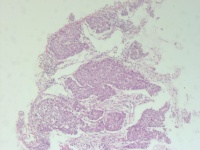

性别

男

年龄

56岁

临床诊断

肺占位

一般病史

CT发现右下肺占位性病变

标本名称

纤支镜活检

大体所见

合约1*0.8*0.3cm灰红组织多枚

图1

鳞癌

主要是鳞,不过图5图6那样的区域有没有腺不好说,最好标一下。